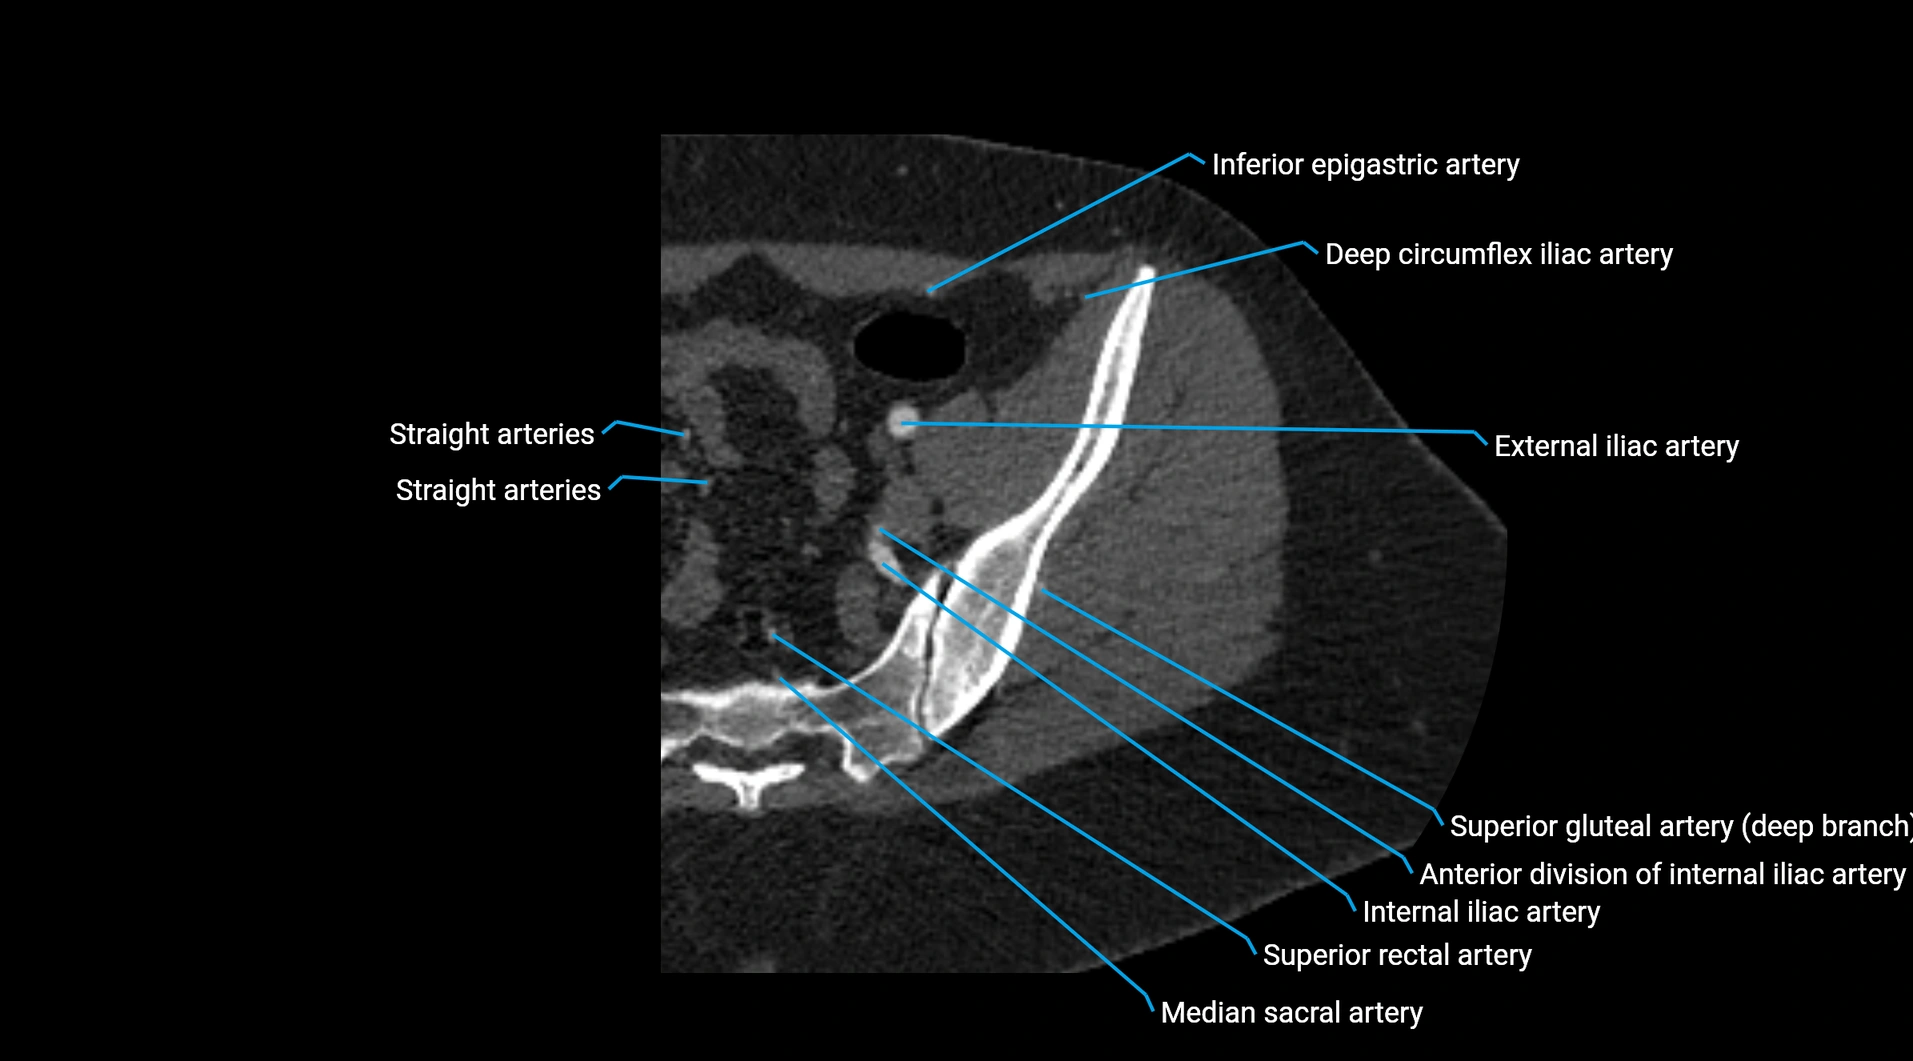

Contrast-enhanced CT (CTA):

• Gold standard for abdominal aortic imaging

• Provides excellent detail of lumen, wall, aneurysm, thrombus, and branch vessels

• Multiplanar and 3D reconstructions help in aneurysm measurement, stent graft planning, and dissection evaluation

• Detects acute rupture, traumatic injury, or occlusion with high sensitivity